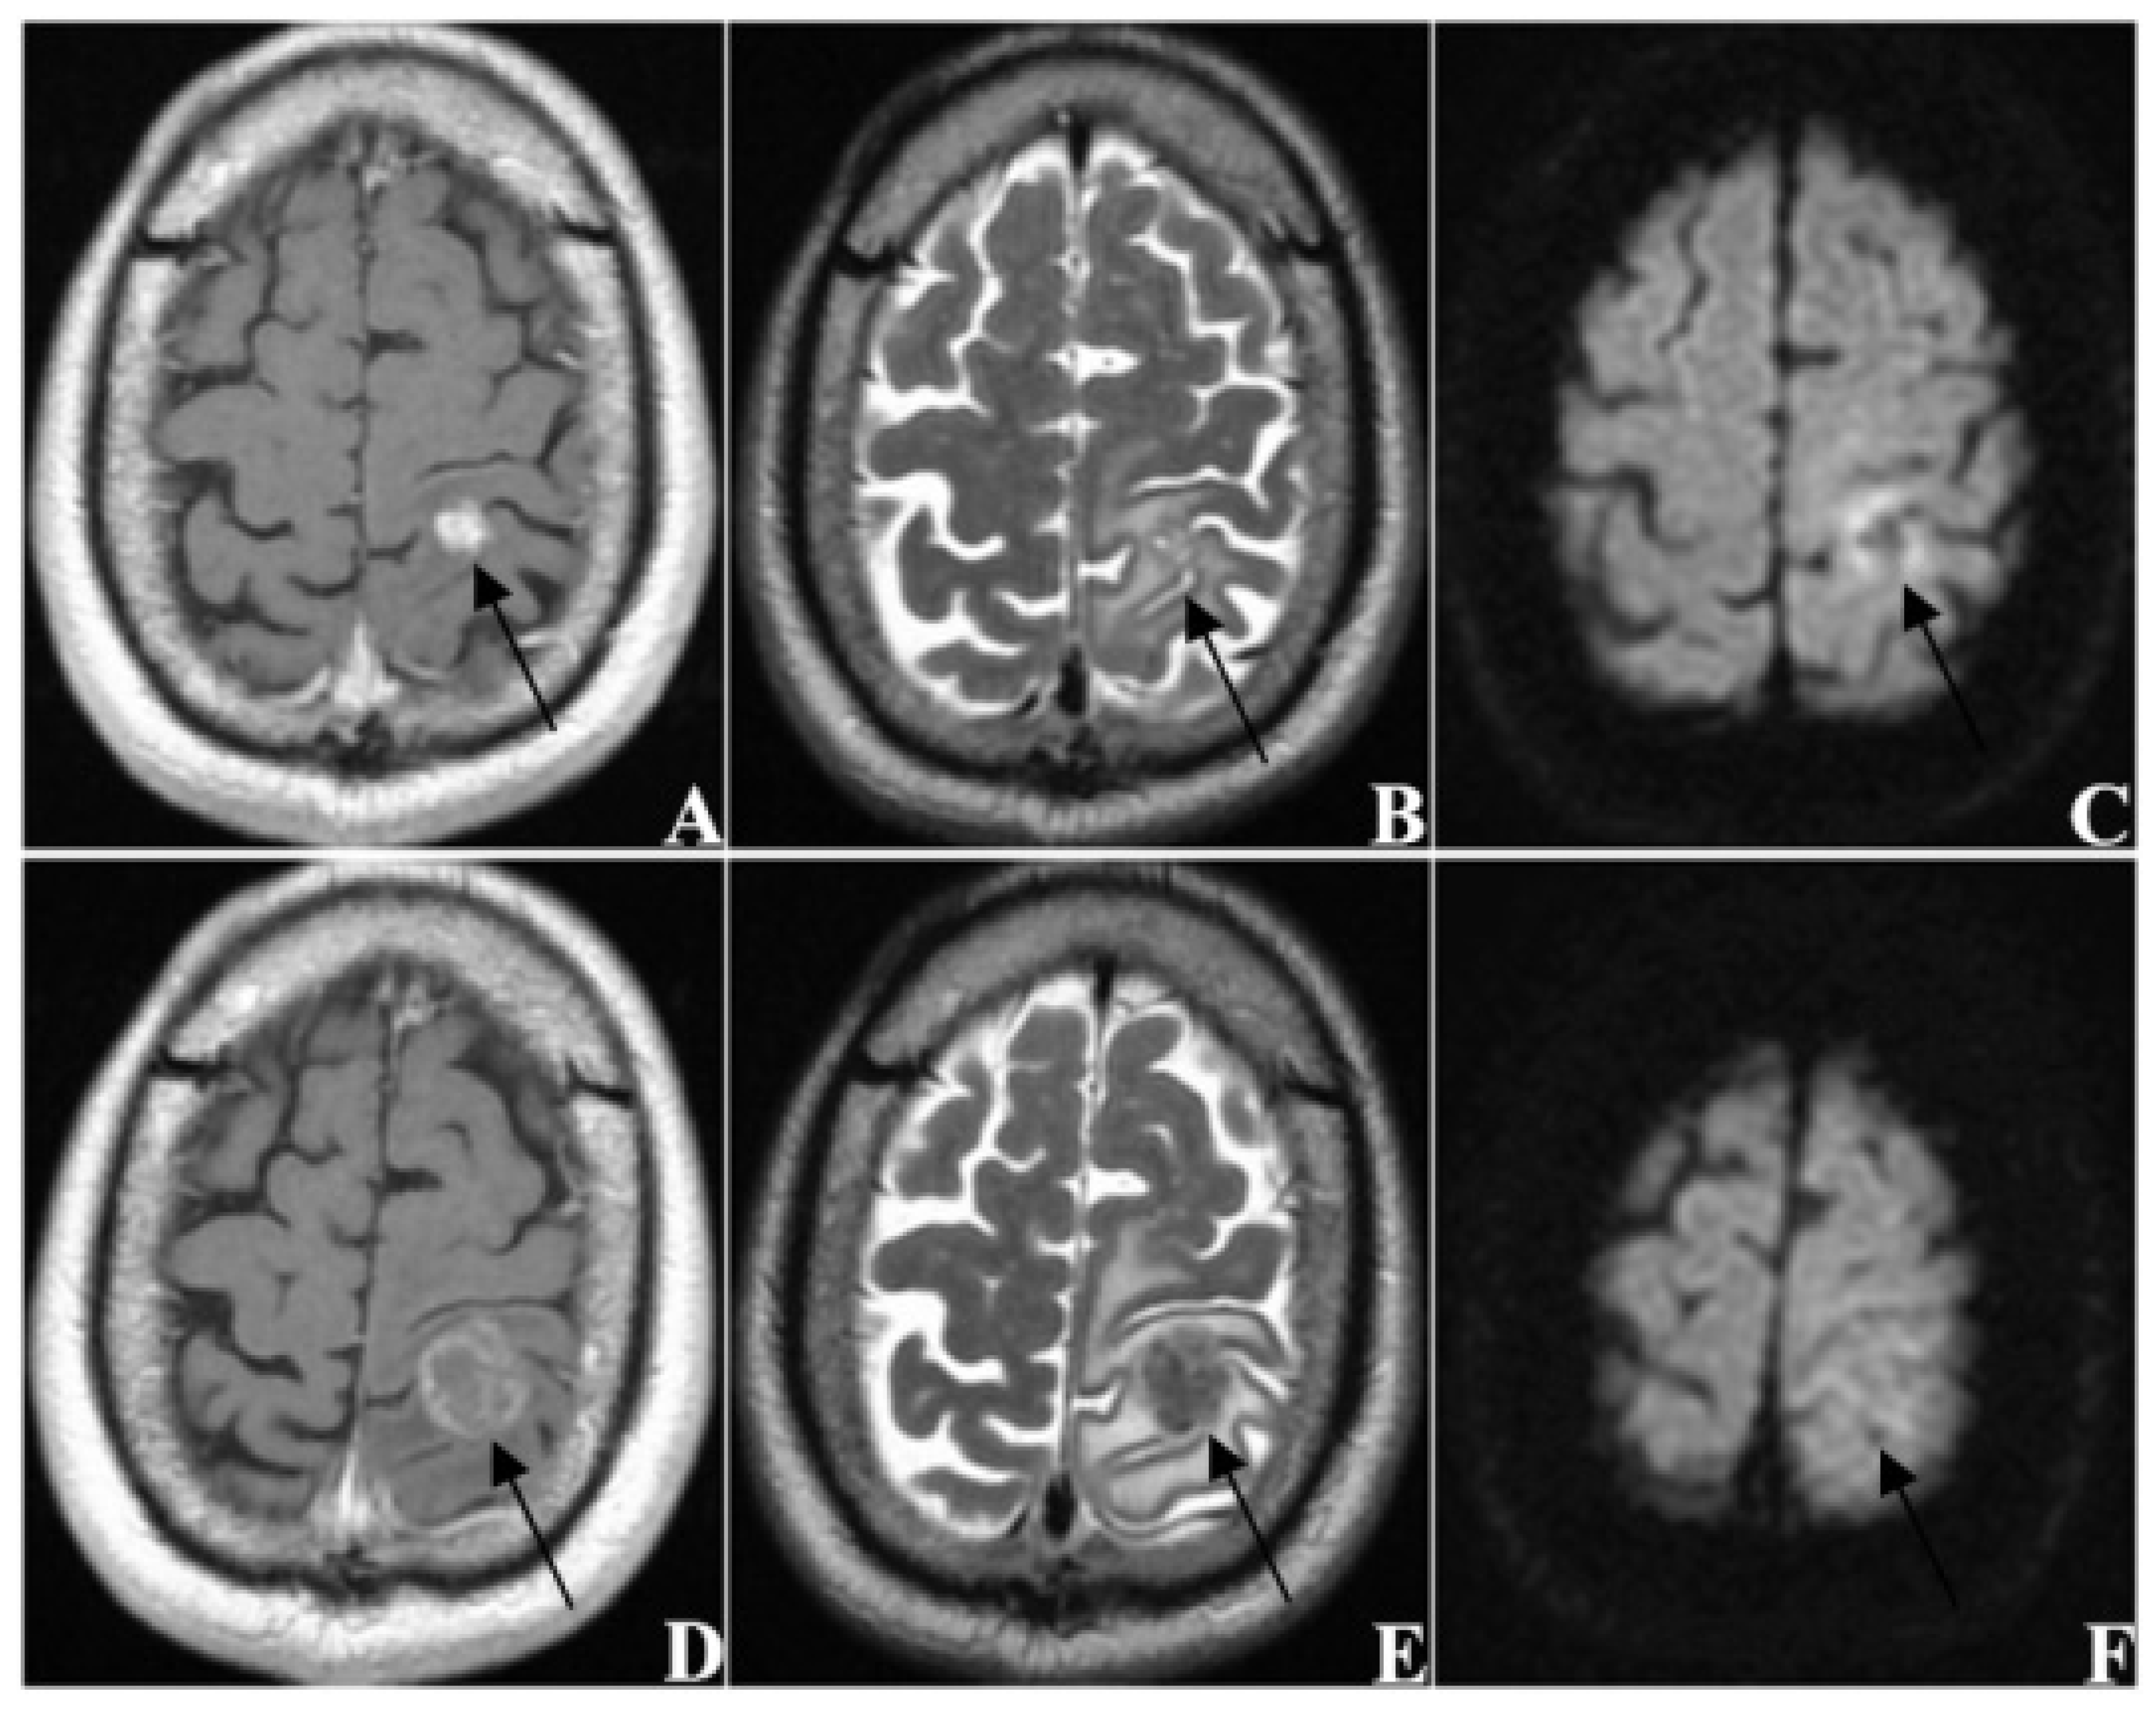

| enhanced pattern | |

| homogeneous | 113 (35.0) |

| heterogeneous | 105 (32.5) |

| ring-like | 105 (32.5) |